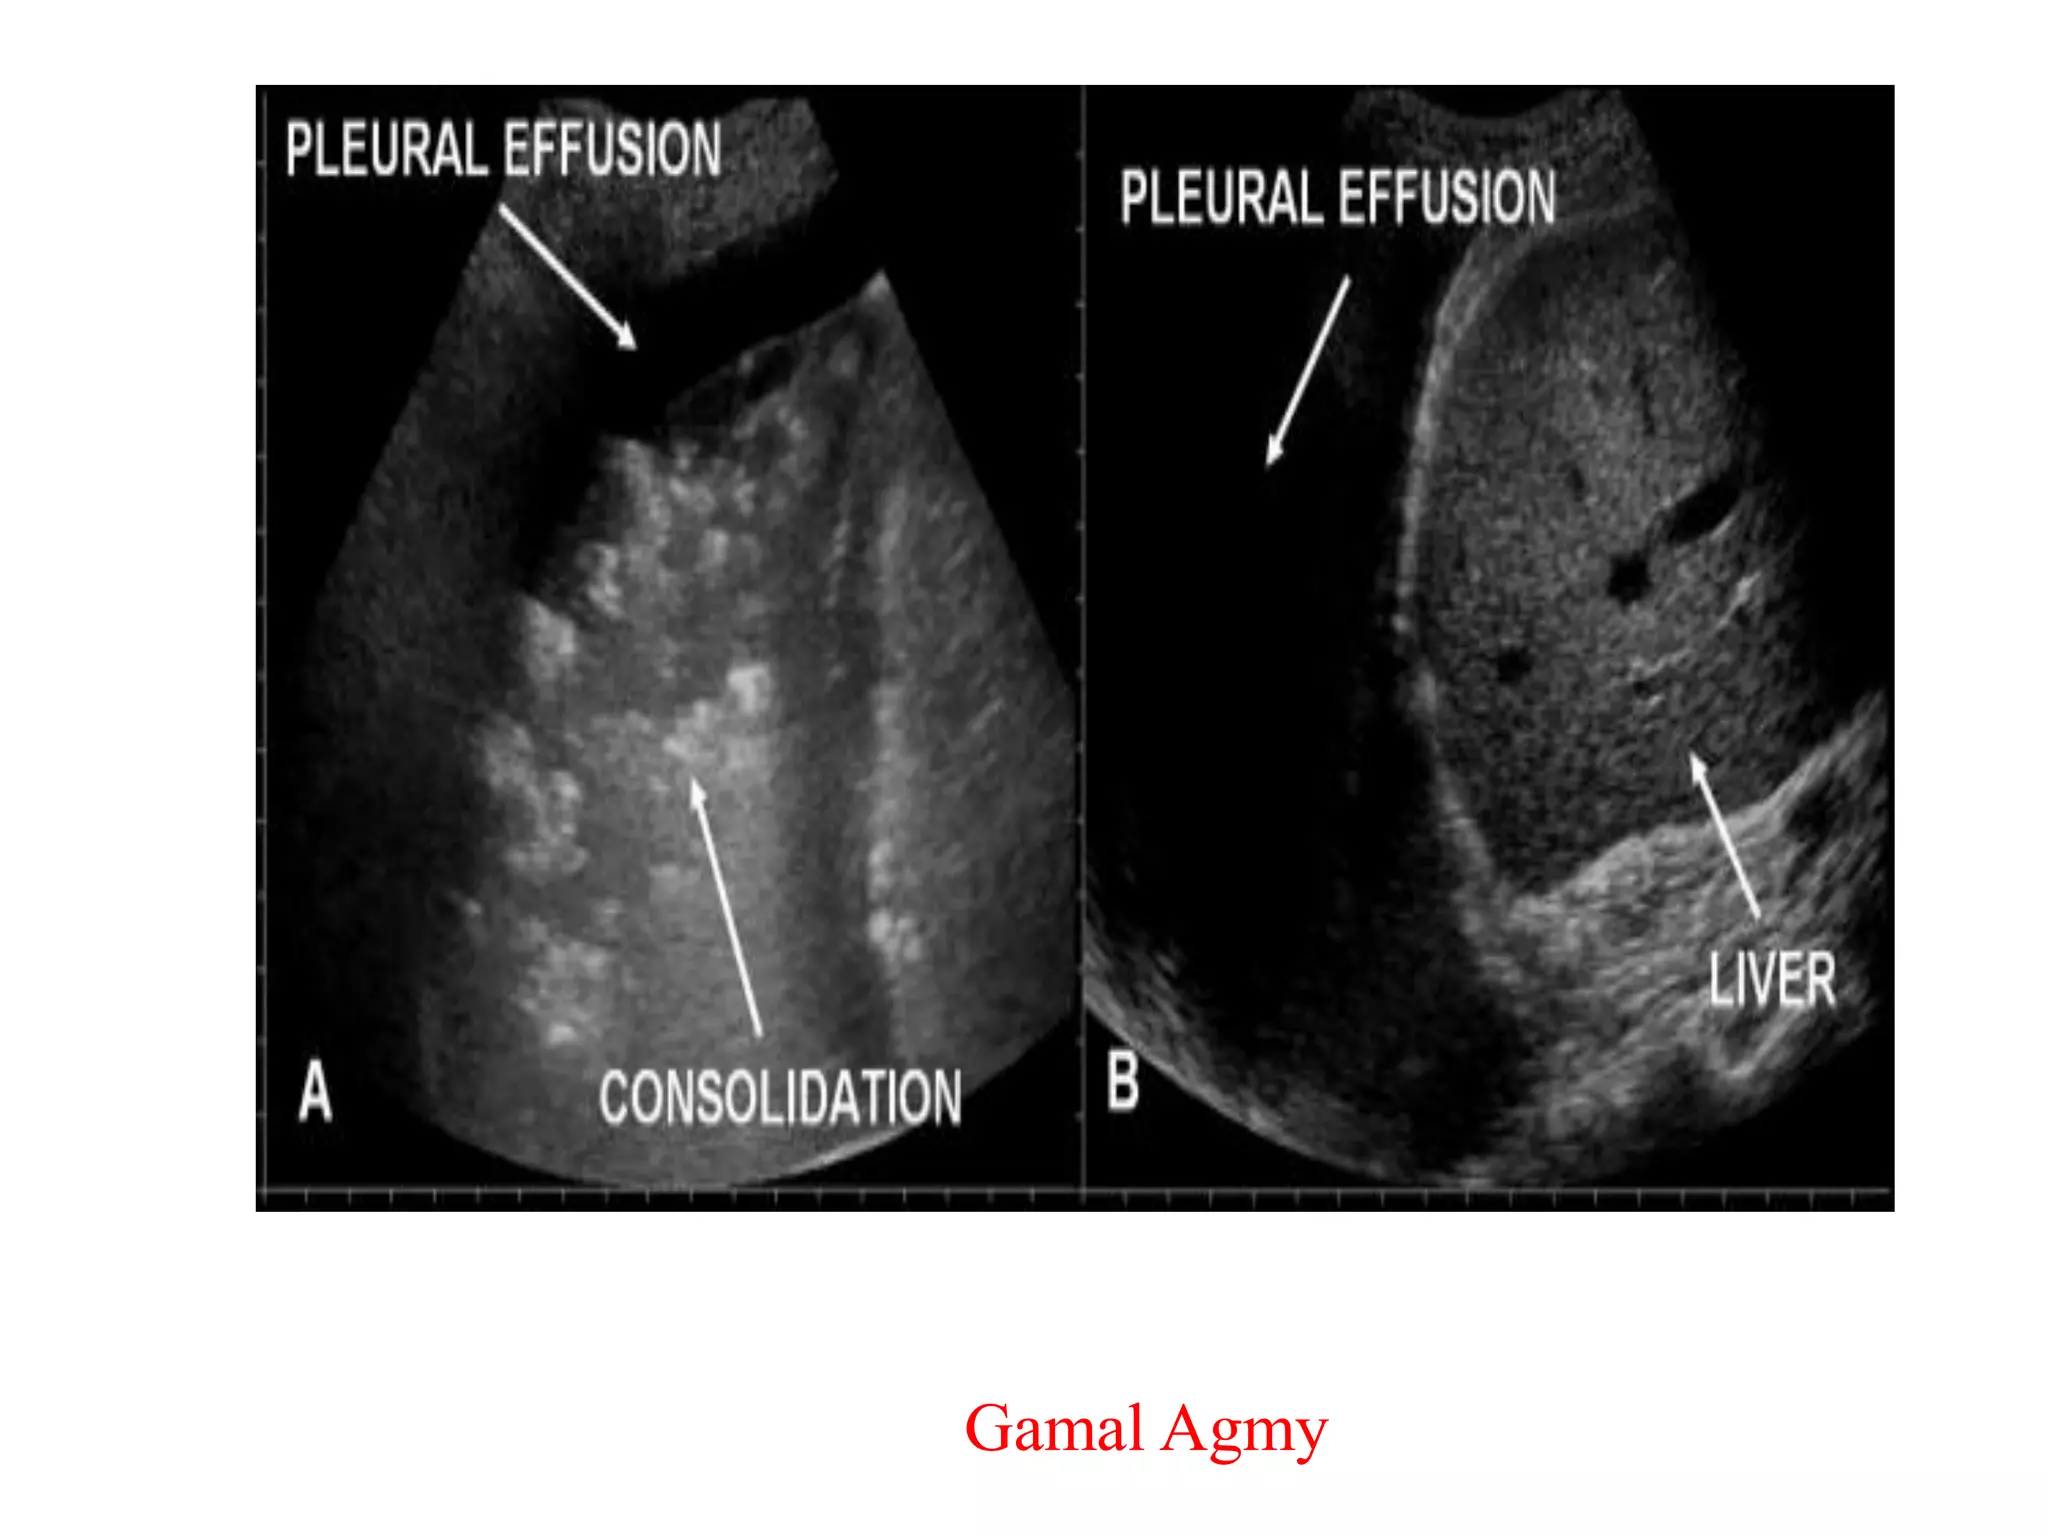

Pulmonary embolism. A 1.2 – 1.5 mm triangular subpleural

lung consolidation. B. Vascular sign at the margin, not central

• On color Doppler sonography,

PE-based peripheral lesions do

not show flow signals inside,

a phenomenon defined as

“consolidation with little

perfusion”